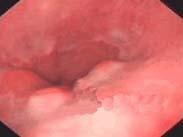

• Barrett食管

628健康網為您分享有關Barrett食管的癥狀,Barrett食管的治療方法,Barrett食管的預防知識,Barrett食管的癥狀圖片,Barrett食管吃什么藥...